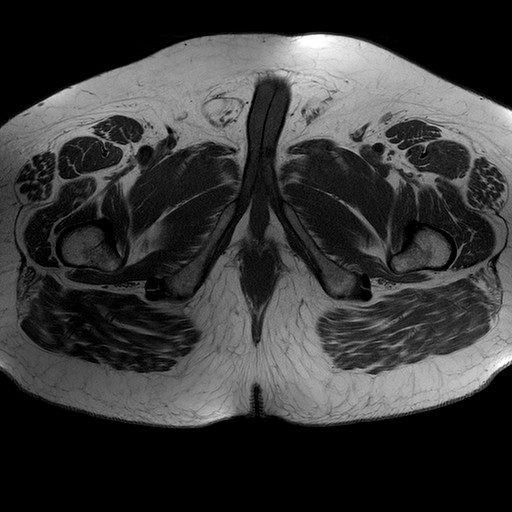

Esami: RMN BACINO

Evidenti e simmetriche alterazioni osteofitosiche in regione coxo femorale con riduzione delle rime articolari. Degenerazione completa del cercine glenoideo. Non attuali segni di versamento articolare. Non segni di edema osseo che escludono attuale algodistrofia od osteonecrosi. Lieve e simmetrica riduzione del trofismo della muscolatura glutea.